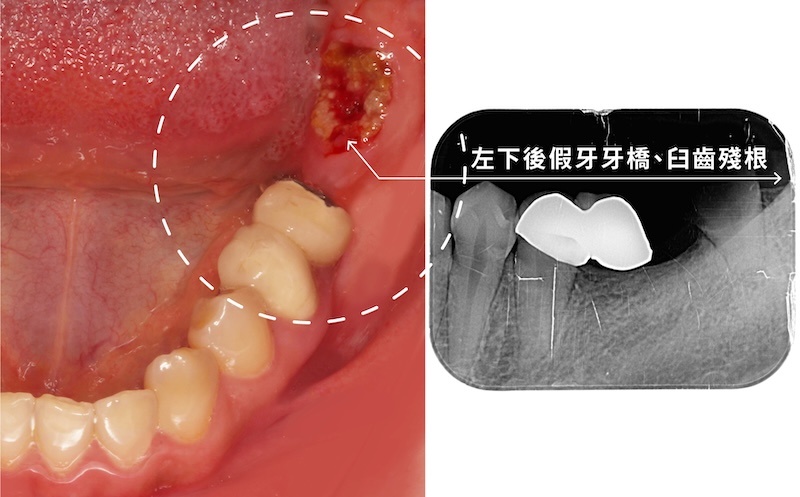

Miss Sung 最初因左下後牙區缺牙及舊式牙橋清潔不易,導致臼齒蛀斷成為殘根,才來作植牙諮詢評估。

雖然患者自覺無明顯症狀,但經診斷患有全口輕微牙周病,伴隨局部深牙周囊袋與初步齒槽骨流失。此外,由於缺牙多年,患處已出現牙齦萎縮及角化牙齦不足的問題,可能影響未來植牙的長期穩定性。

拔除殘根後,採用舒眠植牙手術置入兩支人工牙根。隨後執行「游離牙齦移植術」增加牙肉寬度與厚度,預防植體周圍發炎。